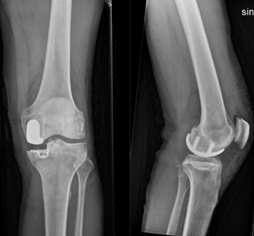

Lena 54 år. Gift, bor på lantgård, ffa mjölkbonde men sköter en del skog. Tidigare väsentligen frisk, inga signifikanta knätrauma (intakt ACL). Har gått artrosskola. Går med hälta, BMI 24, vältränad för åldern. Använder inga gånghjälpmedel men har mycket belastningssmärta distinkt medialt i vänster knä.

Röntgen ser helt okej ut men finns problem där tibia och femur möts på medialsidan

Åtgärd? Varför denna åtgärd?

A

• Opererad med uni-protes (unikompartmentell protes) (bara 10 % får denna)

o Intakt främre korsband

o Inte för stor preop HKA-vinkel